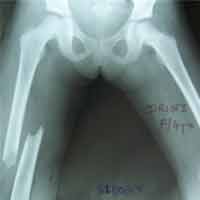

Case:8 Polytrauma

Patient having closed segmented fracture midshaft & lower 1/3 Tibia with closed fracture superior & inferior pubic rami right side with pelvis fracture following vehicular accident wastreated with intramedullary nail for fracture tibia and external fixator for fracture pelvis.

Pre-Op

Immdiate Post-op

Post-op Lateral

Lat-Post Fall

Ex fix with frame

Post-op 1 and half months follow-up

Post Uninon-3Months